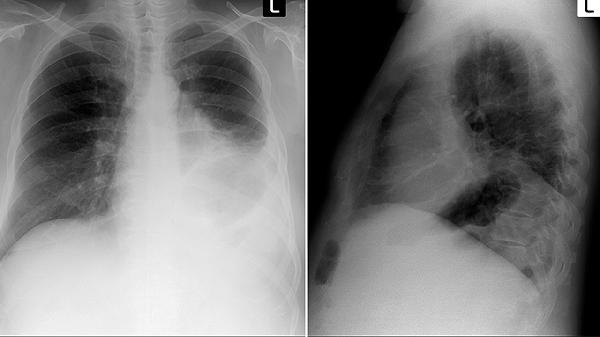

肺部阴影的原因揭晓 这几种情况会导致肺部阴影出现

肺部阴影可能由肺炎、肺结核、肺肿瘤、肺栓塞、肺纤维化等疾病引起。肺部阴影通常通过影像学检查发现,具体原因主要有肺部感染、肺部良性病变、肺部恶性肿瘤、肺血管疾病、职业性肺病等因素。

细菌性肺炎可能导致肺部出现片状阴影,患者常有发热、咳嗽、咳黄痰等症状。病毒性肺炎可表现为双肺多发磨玻璃样阴影,伴有呼吸困难。真菌感染多见于免疫力低下人群,影像学可见结节或空洞样改变。治疗需根据病原体选择抗生素、抗病毒或抗真菌药物,如阿莫西林克拉维酸钾片、磷酸奥司他韦胶囊、伏立康唑片等。

肺错构瘤在CT上表现为边界清晰的圆形阴影,内含脂肪或钙化成分。炎性假瘤多与既往感染相关,呈孤立性结节。肺囊肿为先天性发育异常,可见薄壁囊性阴影。多数良性病变无需特殊治疗,定期随访即可,若出现压迫症状可考虑手术切除。

原发性肺癌常表现为分叶状结节或肿块,可能伴有毛刺征和胸膜凹陷。转移性肺癌多为多发性结节,原发灶常见于乳腺、结肠等部位。小细胞肺癌生长迅速,早期即可发生转移。确诊需依靠病理活检,治疗包括手术、化疗、放疗及靶向治疗等综合手段。

肺栓塞导致肺动脉阻塞,CT肺动脉造影可见充盈缺损。肺梗死表现为楔形实变影,基底朝向胸膜。肺动静脉畸形呈异常血管团,可能引起咯血。抗凝治疗是肺栓塞的基础治疗,严重病例需溶栓,常用药物包括低分子肝素钙注射液、华法林钠片等。

尘肺病可见弥漫性结节和纤维化阴影,与长期吸入粉尘有关。矽肺特征性表现为肺门淋巴结蛋壳样钙化。职业性哮喘可能导致暂时性阴影。预防关键在于职业防护,治疗以对症支持为主,晚期可考虑肺移植。确诊患者应调离粉尘作业岗位。

发现肺部阴影应完善胸部CT、肿瘤标志物、支气管镜等检查明确诊断。日常生活中需戒烟,避免接触粉尘和有害气体,注意观察咳嗽、胸痛等症状变化。高危人群应定期进行低剂量CT筛查,确诊后严格遵医嘱治疗,不同病因的肺部阴影预后差异较大,早期干预可改善治疗效果。